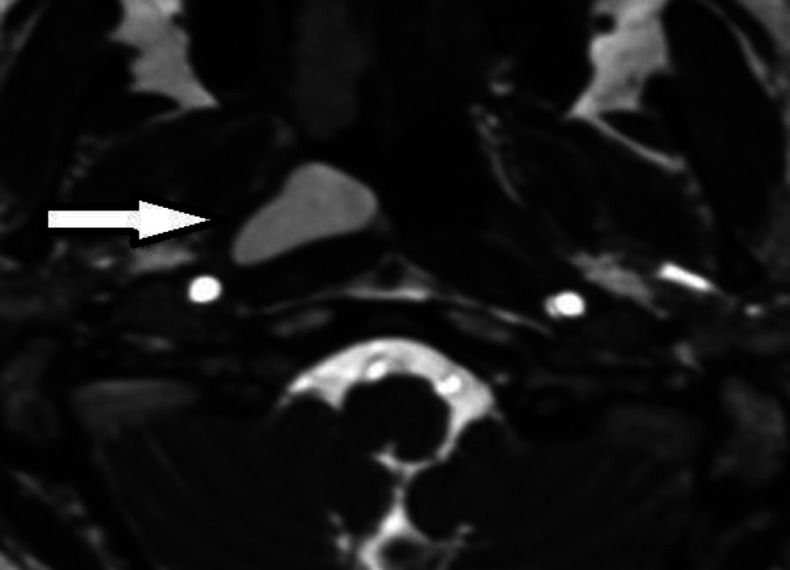

简介大多数鼻咽囊肿无症状且罕见。然而,这些病变很少在常规内窥镜检查和造影检查中被发现。上鼻咽 Thornwaldt 囊肿是一种先天性粘膜良性囊肿。甚至更少见的是,它们会引起不明原因的鼻窦症状,如鼻出血、视力问题和鼻腔堵塞:病例报告:我们在此报告了一例冠状病毒感染后新发听力损失的病例,其影像学检查显示鼻咽部肿块:结论:感染冠状病毒-19 后,我们应考虑高危患者的腮腺囊肿和 Thornwaldt 囊肿。结论:感染科维-19 病毒后,我们应考虑高危患者的腮腺囊肿和 Thornwaldt 囊肿,另一方面,科维-19 病毒感染后的渐进性听力损失也可能是这类囊肿激活所致。

Case report: Here, we report a case with new-onset hearing loss after the coronavirus infection, in which his imaging investigation showed a nasopharyngeal mass.